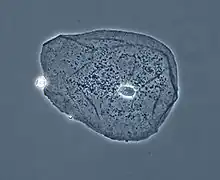

Le microscope à contraste de phase est un microscope qui exploite les changements de phase d'une onde lumineuse traversant un échantillon.

Le microscope à contraste de phase est très utilisé en bactériologie grâce à sa particularité de révélation des objets peu opaques, notamment dans le domaine dentaire dans la recherche en parodontologie, recherche de la flore bactérienne de la gencive pour détecter et suivre la maladie parodontale ou parodontite.